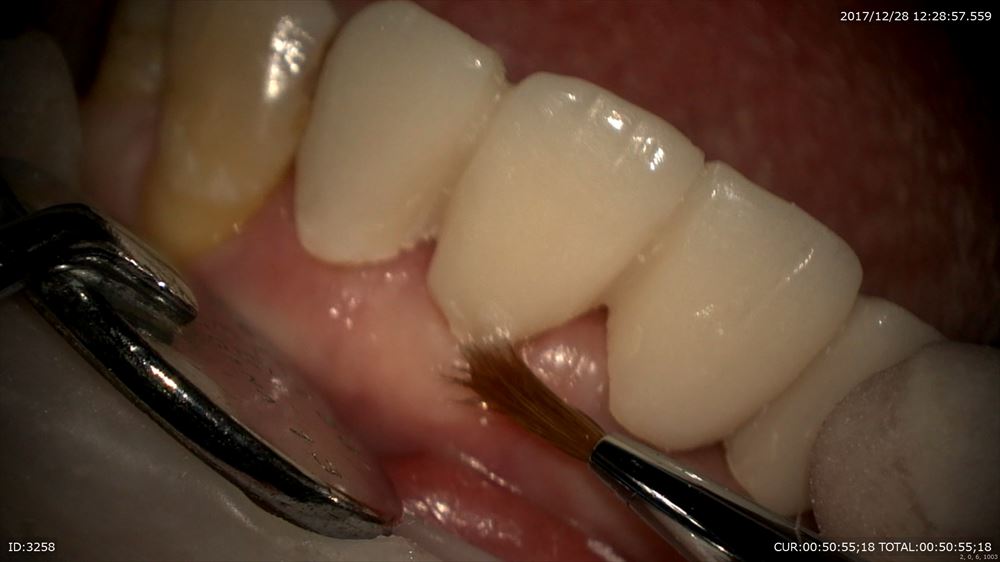

そして仮歯の作成

ここから

こんな感じ。

仮歯ですが機能はしっかりしています。お正月も安心!!